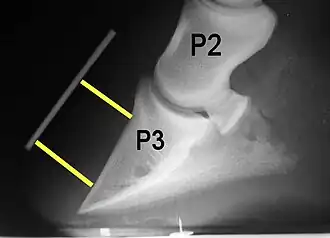

Radiograph of a horse hoof showing marked separation of the hoof from the coffin bone with evidence of roation and sinking, comaptible with active severe laminitis. P2 designates the middle phalanx, or pastern bone, and P3 designates the distal phalanx, or coffin bone. The yellow lines mark the distance between the top and bottom part of the coffin bone relative to the hoof wall, showing marked widening of the hoof-lamellar zone, with the distal (bottom) of the coffin bone rotated away from the hoof wall.